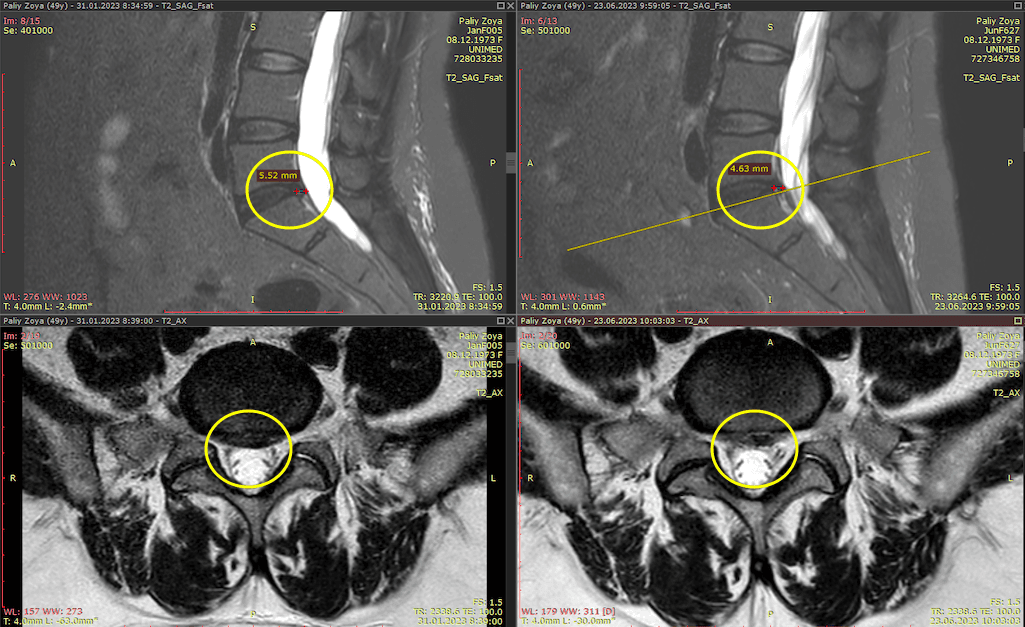

Метод лікування грижі шляхом стимуляції резорбції в Україні був впроваджений у 2020-2021 роках.  Алгоритм оцінки грижі на предмет резорбції, що використовується у клініках – є авторським, розроблений лікарем Боханом А.Ю.